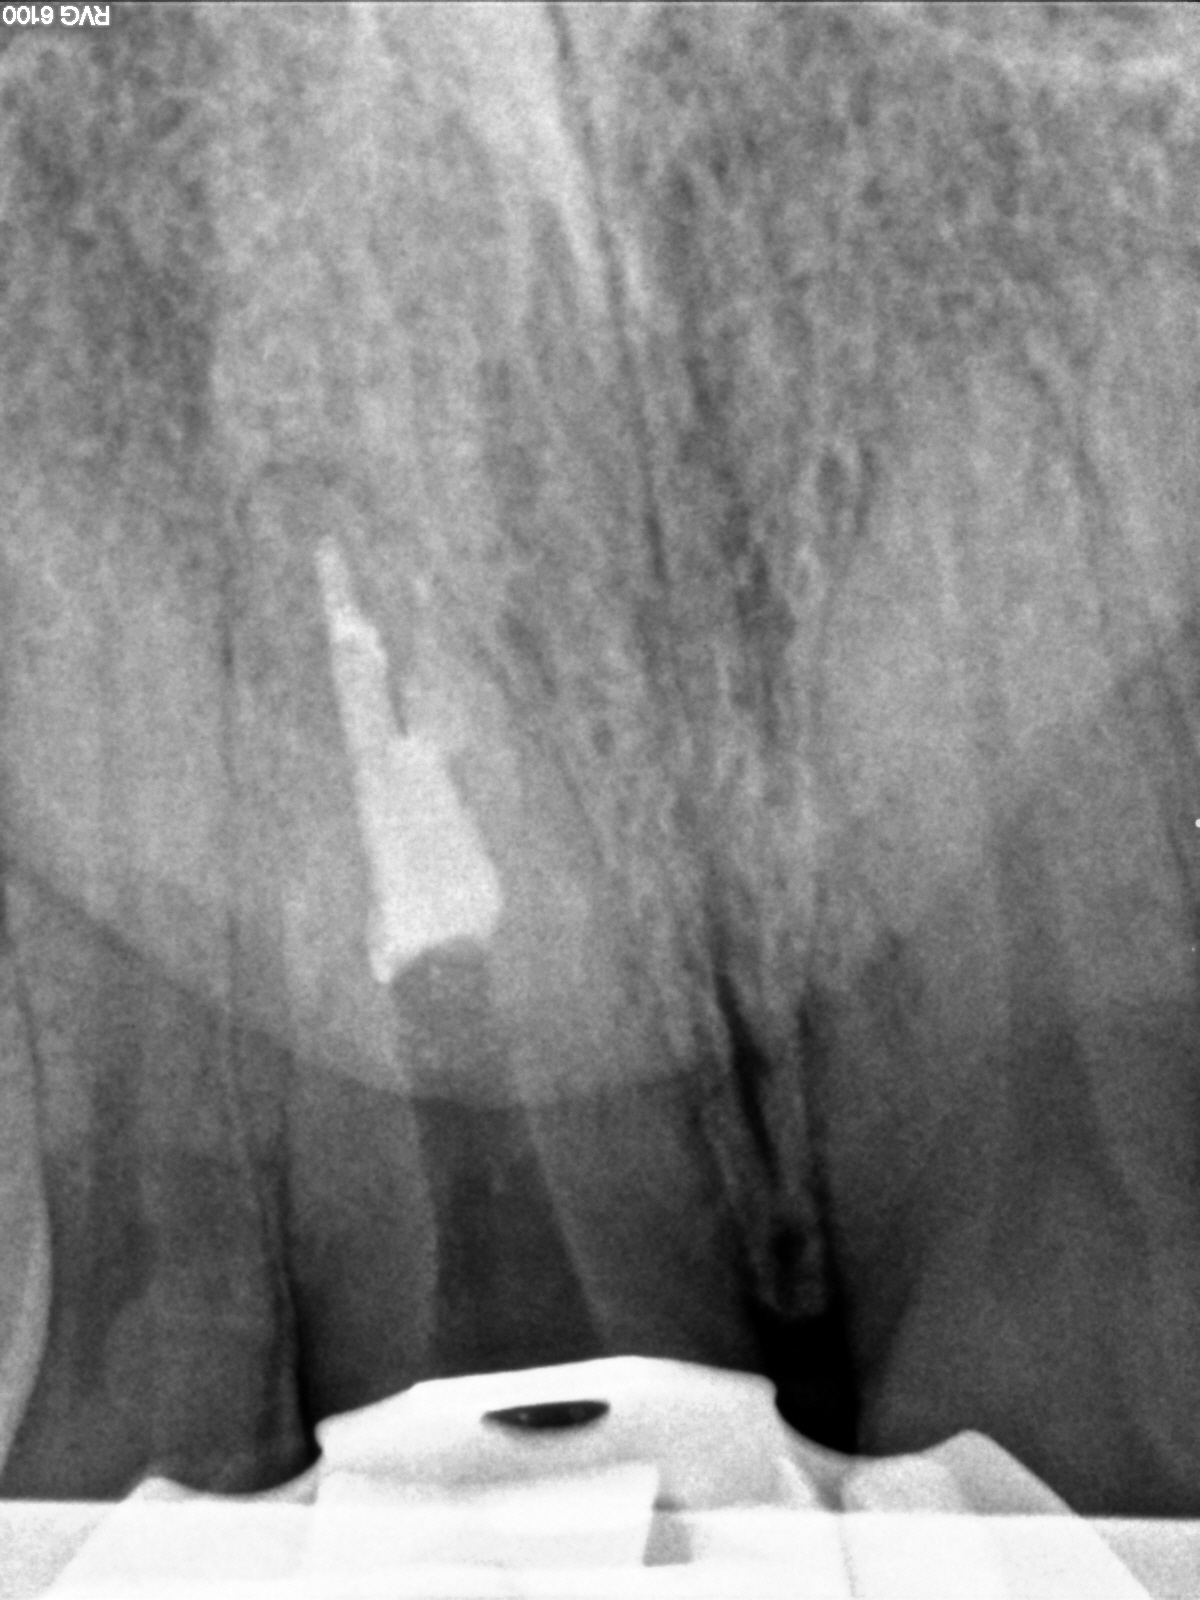

R11

Manchmal… (2)

Backfill